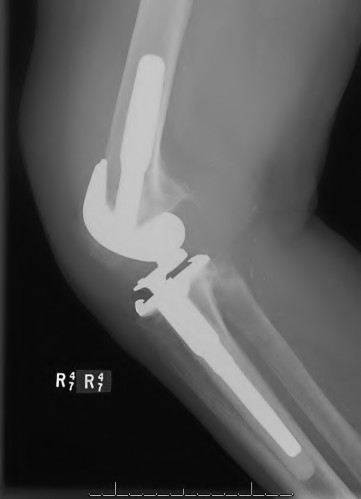

A 60-year-old male tennis player undergoes a unicompartmental knee arthroplasty (UKA) shown in Figures A and B. Which of the following statements regarding this procedure is true?

Figures A and B depict radiographs of a unicompartmental knee arthroplasty (UKA). UKA kinematics have been shown to most closely approximate native knee kinematics.

In an in vitro cadaver study, Patil et al found that TKA significantly changed knee kinematics while the unicompartmental replacement preserved normal knee kinematics.

Fisher et al performed a retrospective study comparing the short-term outcomes of small-incision unicompartmental knee arthroplasty (UKA) with standard total knee arthroplasty (TKA) in 91 consecutive patients older than 70 years. They found: 1) Blood loss was significantly more for the TKA group, as was the need for blood transfusion. 2) Patients with unicompartmental replacements had a much quicker return of function and discontinuation of pain medication. 3) While knee scores and ROM were similar preoperatively, both were better in the unicompartmental group at each postoperative time interval. 4) Narcotic use and length of hospital stay were also significantly less for the unicompartmental group. Therefore answers 2,3,4 and 5 are false.